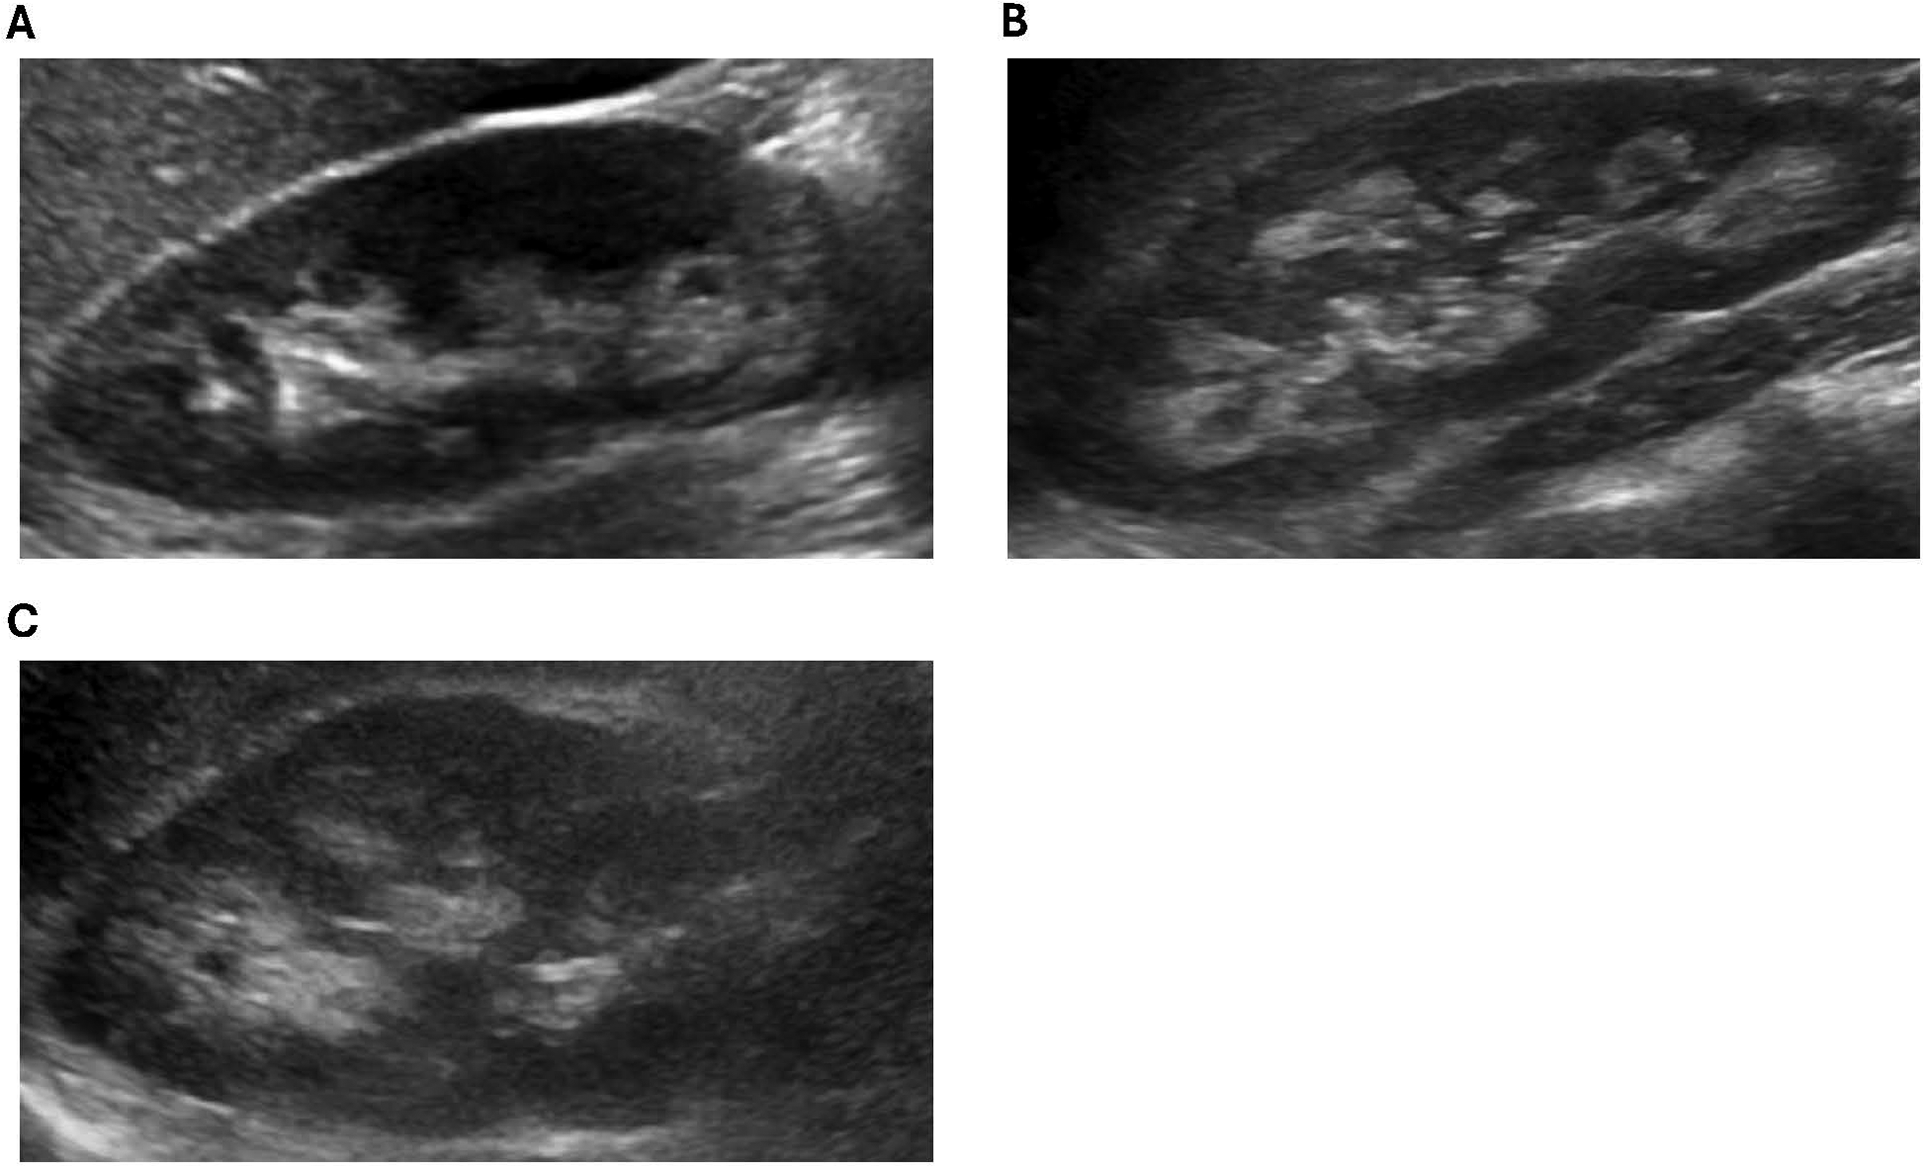

Of the 13 XLH patients in our cohort, 3 were diagnosed with nephrocalcinosis during the study period. Further details regarding these patients are featured in Table 2. All three patients were female and had a family history of XLH. Typical images from our cohort with nephrocalcinosis are shown in Figure 1.

Figure 1

Representative ultrasound images from XLH study patients with NC. (A) Patient 1: increased echogenicity surrounding the medullary pyramids (grade 1). (B) Patient 2: increased echogenicity around and starting to incorporate inside the pyramids (grade 2). (C) Patient 3: increased echogenicity around and starting to incorporate inside the pyramids (grade 2).